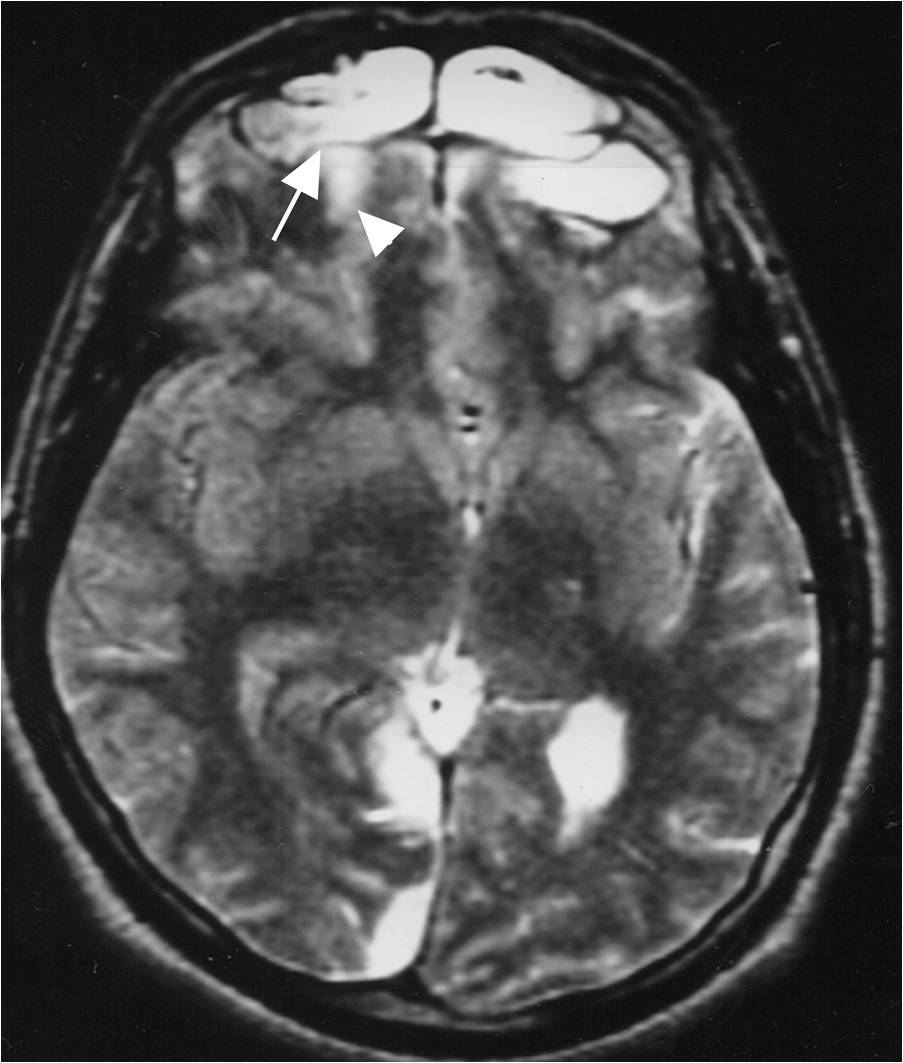

ae Cerebral infarction complicating tuberculous meningitis in a... Download Scientific Diagram Ct Scan Meningitis mri is superior to ct scanning in the evaluation of patients with suspected meningitis, as well as in demonstrating leptomeningeal. Your doctor will flex your leg at the knee and. bacterial meningitis reflects infection of the arachnoid mater and the csf in both the subarachnoid space and the. computerized tomography (ct) or magnetic resonance imaging (mri) scans. Ct Scan Meningitis.

Cerebrovascular complications in tuberculous meningitis—A resonance imaging study in 90 Ct Scan Meningitis leptomeningitis, which is more commonly referred to as meningitis, represents inflammation of the subarachnoid space (i.e. neck stiffness and involuntary bending of the knees and hips can indicate meningitis. bacterial meningitis reflects infection of the arachnoid mater and the csf in both the subarachnoid space and the. more patients with meningitis are undergoing ct and the. Ct Scan Meningitis.

Fig. 6.5, [Proven tuberculous meningitis with multiple...]. Diseases of the Brain, Head and Ct Scan Meningitis leptomeningitis, which is more commonly referred to as meningitis, represents inflammation of the subarachnoid space (i.e. neck stiffness and involuntary bending of the knees and hips can indicate meningitis. bacterial meningitis reflects infection of the arachnoid mater and the csf in both the subarachnoid space and the. mri is superior to ct scanning in the evaluation. Ct Scan Meningitis.